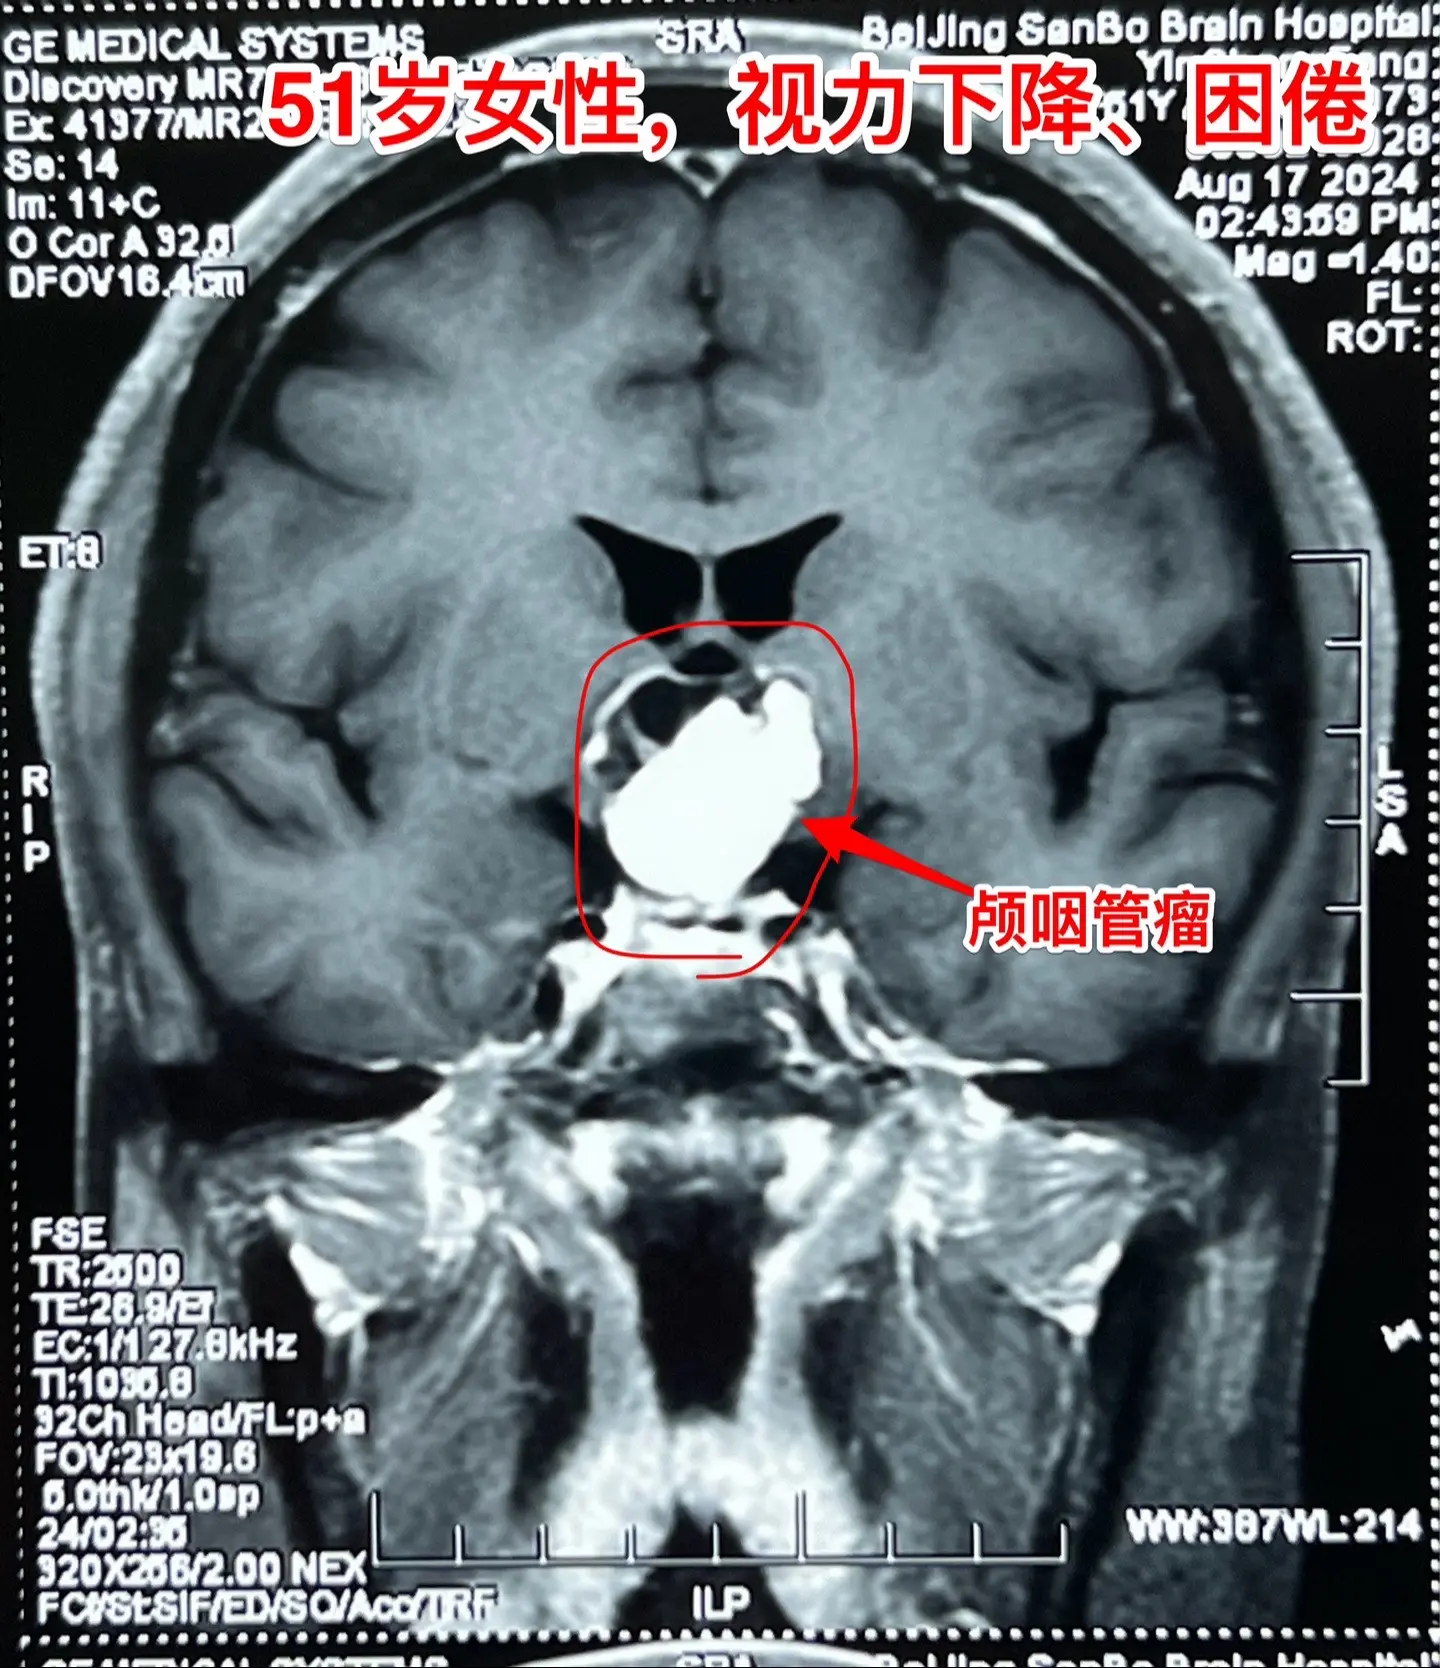

视频中展示出来的是第一个和第三个病人的影像学资料。

第一个病人女性,51岁,山东人。患者的弟弟就是神经外科医生。病人因为视力下降、困倦、无精打采到医院检查发现颅咽管瘤,是乳头型颅咽管瘤。患者家人一致要求作开颅手术切除颅咽管瘤。今天的手术很顺利,颅咽管瘤得到完全切除,晚上病人作完了CT就从ICU转到普通病房了。